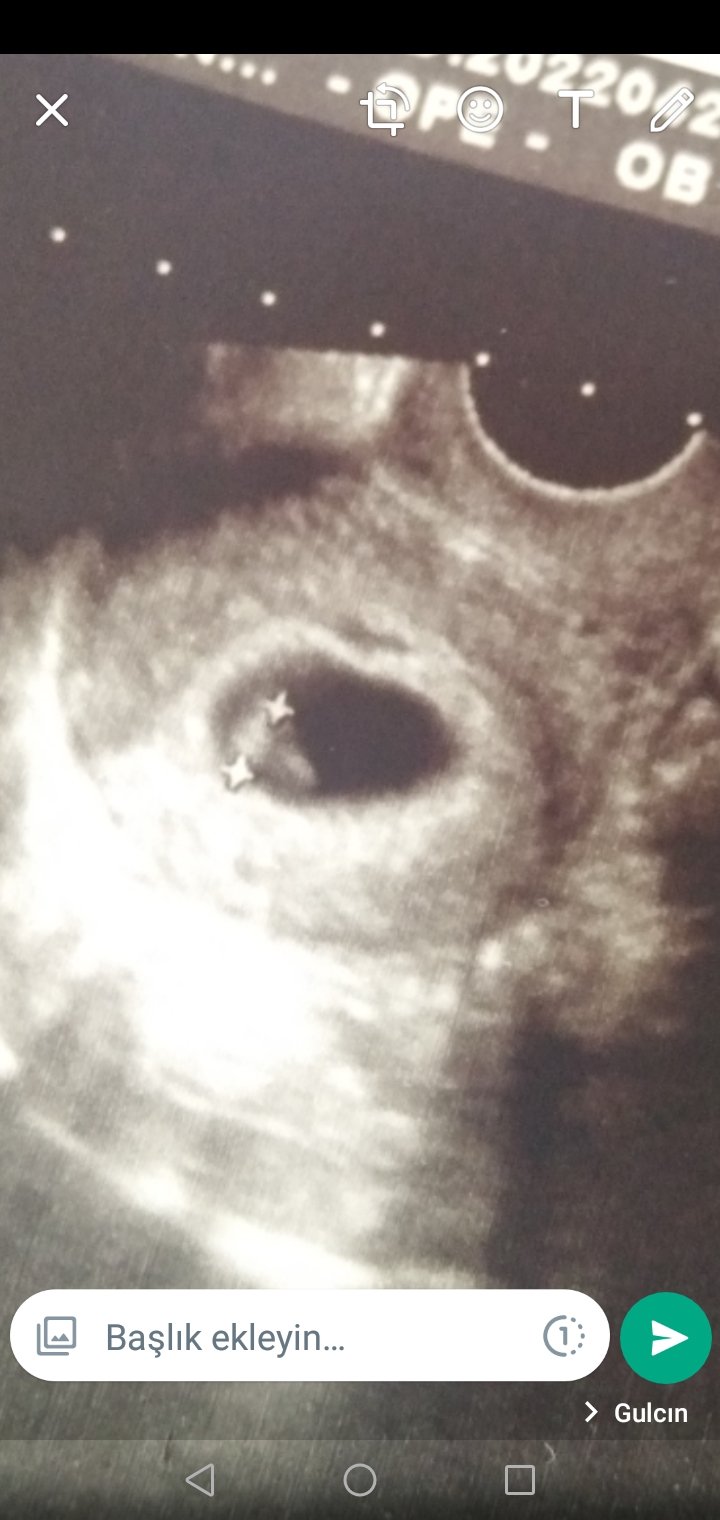

Kaç haftalikken gittin cnm bana da ufak olduğunu söylediler 6+4 kesenin içinde bebeği gördün ozmn ultrason resmin var mi bnm bu cnm bence vardır ufak olduğu için göstermedi Altan baktı birde cnm kesem göbekten gözüktü içinde bebek görememisti sonra dan Altan bakınca gözüktü buda minigimin görüntüsü

Ekli dosyalar

• Screenshot_20220422-111207.jpg

Screenshot_20220422-111207.jpg

414.4 KB · Görüntüleme: 179